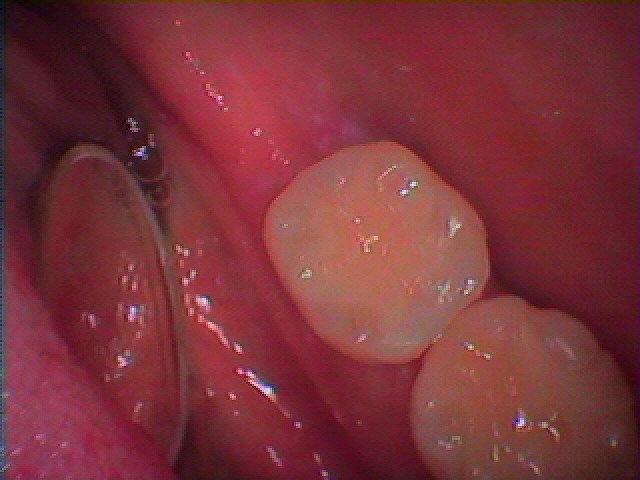

セラミックを入れていきました

セレックセラミックにて修復しています

本来の歯の通りとなりました